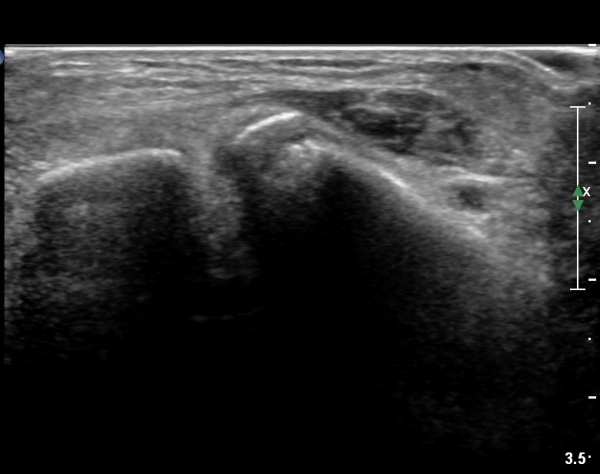

she revealed limping gait. on examination, there is swelling around ankle with limited ankle motion, localized tenderness at distal tibiofibular ligament and ATF ligament.

ÃÊÀ½ÆÄ °Ë»ç